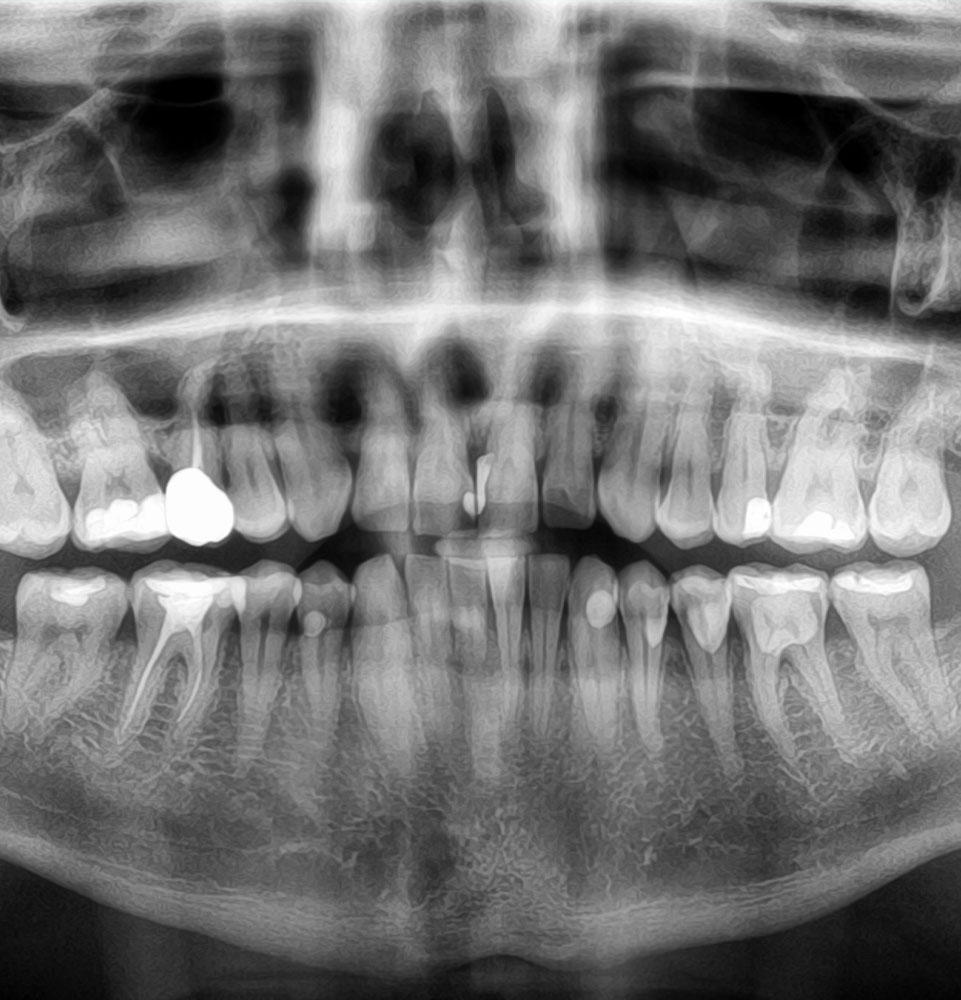

Fractures

Treatment in Morristown, NJ, and Flushing, NY, for fractures to the jawbone, eye sockets, cheekbones, and other facial bones depends on the extent and location of your injury. Facial fractures are treated similarly to any other fracture, by stabilizing the bones with plates, screws, or wires to enhance healing.